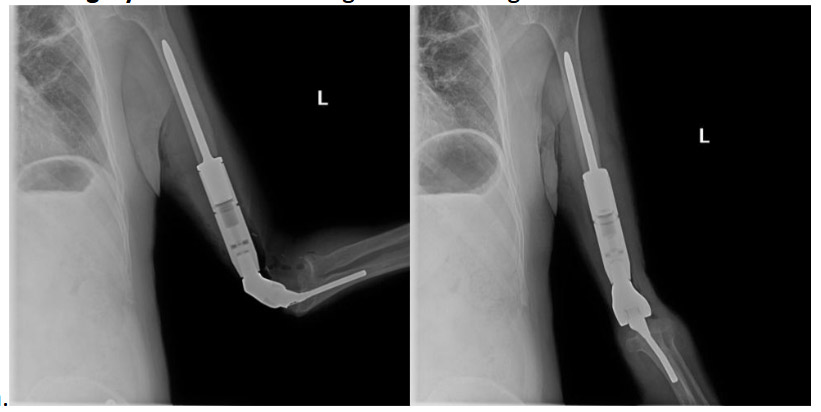

- After the cancerous portion of the bone was removed, a prosthesis was implanted.

Post-surgery: The X-ray shows the implantation of a cemented distal humerus prosthesis.